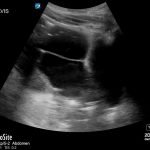

Bedside ultrasound revealed a large volume of free fluid in the right upper quadrant and in the pelvis. The fluid appeared complex with multiple septations. Its appearance was not consistent with ascites or acute intra-abdominal free fluid due to striations and pockets.

The patient was taken to the operating room and found to have a 2 cm pre-pyloric gastric perforation and 3-4 liters of pus in the abdomen. Severe intra-abdominal infections as was found in this patient carry a mortality rate of 30-50%.1 In the absence of pneumoperitoneum found on plain films, bedside ultrasound can be used to confirm intestinal paresis and intraperitoneal fluid suggesting a perforated viscous.2 It can also be used with greater sensitivity than radiography (93% vs 79%) to detect pneumoperitoneum itself.3 While computed tomography remains the gold standard for diagnosing intra-abdominal abscesses, bedside ultrasound offers a rapid alternative diagnostic modality that can be particularly useful in the hemodynamically unstable patient. The sensitivity of ultrasound for spontaneous (not post-operative) intra-abdominal abscess is 92% with increased sensitivity for finding abscesses located in the right and left upper quadrant and in the pelvis.4 Although bedside ultrasound was unable to diagnose gastric perforation as the specific etiology for the patient’s intra-abdominal abscess, it provided more than ample information to justify an emergent and most likely life-saving exploratory laparotomy.